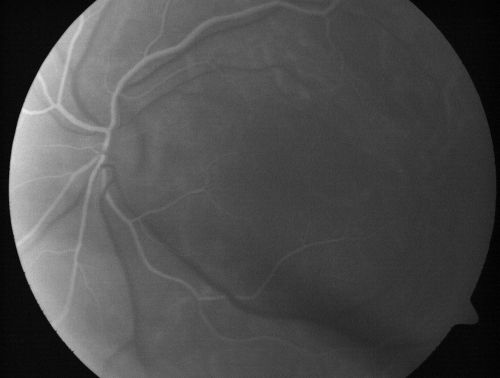

Nanopthalmous (Microphthalmous) Chorioretinal Folds and Choroidal Thickening Both Eyes

67-year-old woman with microphthalmos/nanophthalmos  Her vision has gradually been getting a little bit worse, especially in the right eye.  Also the anterior chamber is getting crowded and there is concern about the need for cataract surgery.  She has one sister and one cousin who also have nanophthalmos.

VISUAL ACUITY:  OD 20/50,  OS 20/80.